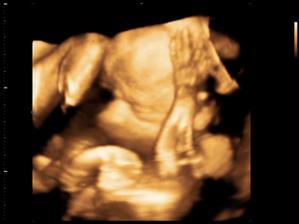

Zda sa ze nase 1. a snad aj posledne ICSI s PK sa podarilo🙂

Onedlho nás uvidíte ako malé bodky na sone,